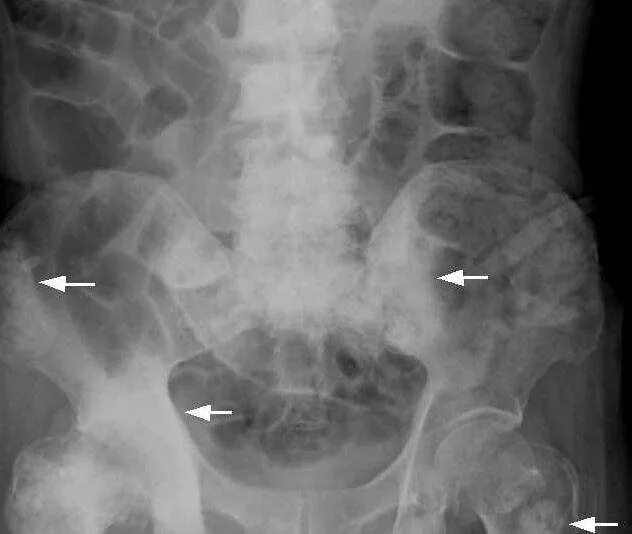

Метастазы в тазобедренном